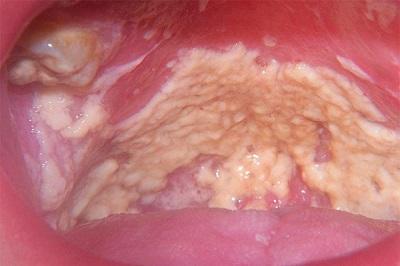

Симптомы кандидоза проявляются стремительно или наоборот медленно. Яркий признак кандидоза — белые новообразования, возникающие на слизистых полостях рта (деснах, небе, языке и внутренних сторон щек). Добавляются болезненные ощущения во рту, возникает зуд и жжение. При глотании боль дает о себе знать, вместе с чувством непроходимости пищи. Во рту возникает металлический привкус, возможно приглушение вкусовых ощущений или их полная потеря. Иногда наблюдается повышение температуры тела.

По белым бляшкам врач может понять, как долго происходит заболевание. При легком отделении образований поверхность под ними будет розоватая и с небольшой отечностью – это говорит о недавнем возникновении заболевания. А вот при запущенной форме поверхность под налетом будет кровоточивой с присутствием маленьких язв.

Симптомы кандидоза полости рта включают в себя:

• болезненные белые пятна (бляшки) во рту, которые можно легко стереть;

• боль и жжение на языке;

• неприятный горький или соленый привкус во рту;

• покраснение и болезненность во рту и горле;

• образование трещин на коже в уголках рта (ангулярный стоматит);

• трудности при глотании.

Типичные проявления молочницы во рту вы можете увидеть на фото справа.